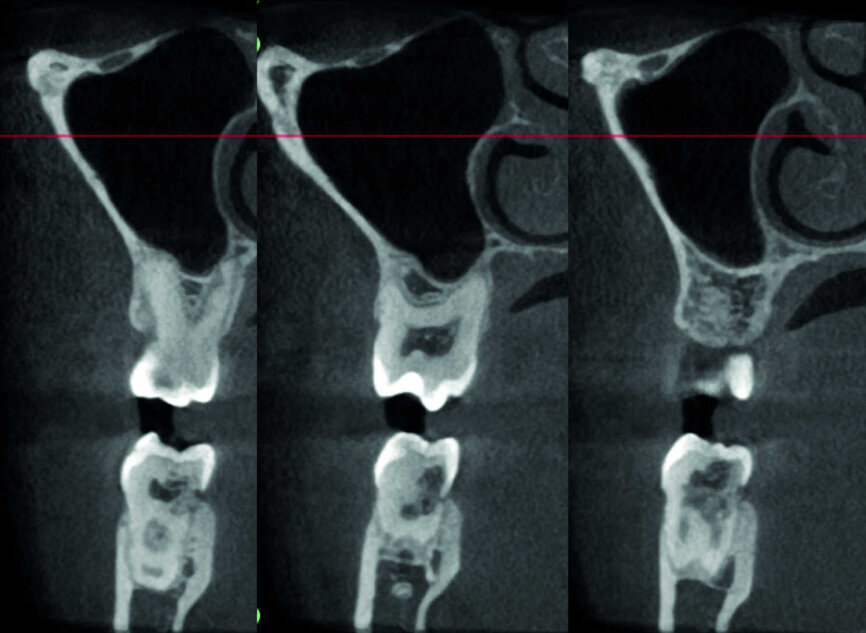

Le cas avec lequel je souhaite commencer mon exposé clinique est un exemple parfait de la difficulté à définir l’origine des symptômes d’un patient, par l’examen d’une simple radiographie intraorale. Non seulement l’examen 2D ne permet pas d’établir avec certitude la présence d’une lésion, mais surtout, il est impossible d’en déterminer la taille, la morphologie et le type. Au contraire, une analyse de l’imagerie 3D offre une image claire de la situation clinique. Chez ce patient, les coupes coronales et sagittales révèlent la présence d’une importante lésion s’étendant de l’apex de la racine mésiale de cette molaire jusqu’à la zone de furcation, tandis que les coupes axiales nous permettent d’analyser précisément l’anatomie endodontique et, en particulier, la forme de la racine mésiale, qui apparaît fusionnée avec la racine palatine. Un panorama complet du cas peut donc guider le processus de décision et orienter le plan de traitement vers une modalité bien précise de traitement (Figs. 1–4).

L’évaluation CBCT préopératoire est utile dans les cas nécessitant une approche chirurgicale, non seulement pour confirmer la présence d’une lésion, mais aussi pour planifier l’intervention et, en particulier, identifier le type d’incision chirurgicale à pratiquer, en fonction de la taille et de l’emplacement de la lésion en question (Figs. 23–25). Le cas spécifique présenté dans cet article est caractéristique de cette situation. La radiographie intraorale n’a pas permis de déterminer l’étendue de la lésion, qui touche non seulement la région apicale de la prémolaire, mais aussi un segment édenté en distal. Cette région doit faire l’objet d’un traitement régénérateur, afin de garantir la cicatrisation appropriée de la zone, suivi par la mise en place d’une membrane. Une approche totalement différente de celle requise pour la chirurgie endodontique doit être utilisée pour protéger le lambeau. Les différentes étapes de l’intervention sont illustrées dans les images peropératoires (Figs. 26–28). L’examen CBCT réalisé 12 mois plus tard, confirme la cicatrisation complète de la lésion apicale et la parfaite intégration de la greffe (Figs. 29–31).